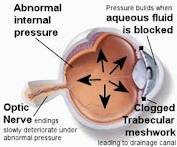

La terapia MLT disminuye la presión intraocular sin dañar el tejido. MicroPulse. Para ello genera pulsos de láser periodos cortos de tiempo, en forma de pulsos, en explosiones de microsegundos de tal forma que el tratamiento sigue siendo eficaz sin producir en el tejido efectos colaterales o daños, que si produce la tecnología láser tradicional.